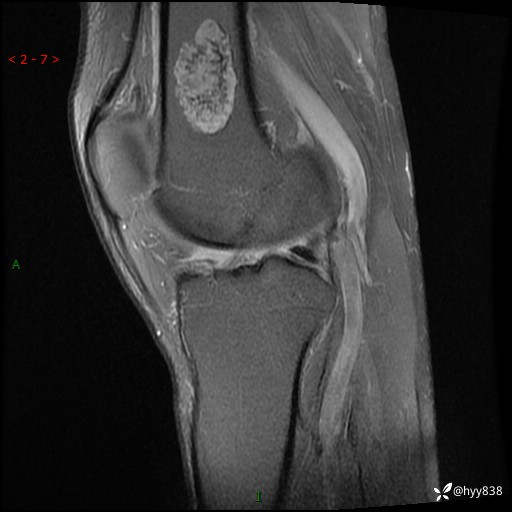

患者性别:男

患者年龄:60岁

主诉:右大腿疼痛不适数月

膝关节平片

MRI

内生软骨瘤 (27)